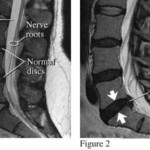

The physical therapy was for my back, which I damaged one day while trying to lift a section of cast-iron sewer pipe that we were removing. I was in bed for a week and then in on and off pain for a year or so after that. An MRI scan ($1,600 for that fun ride) revealed two herniated discs. Finally, one year, we rang up enough medical expenses (On non-renovation issues) so that our deductible was covered. I got 8 sessions of PT that finally put the issue to rest, sort of.